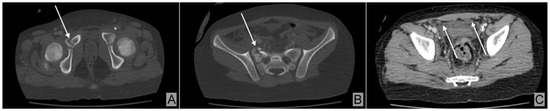

2. Case Description